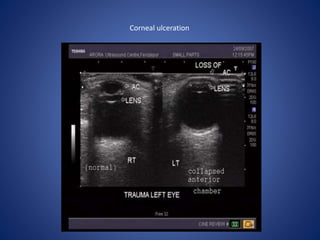

Corneal ulceration

• #15 severe corneal ulceration and collapse of the anterior chamber of the eyeball due to escape of aqueous humor.

• #16 Axial CT. Acute perforation of the lens capsule. The abnormal lens (arrowhead) has low density due to the influx of fluid diluting the normally high protein of the lens. Compare with the opposite side.